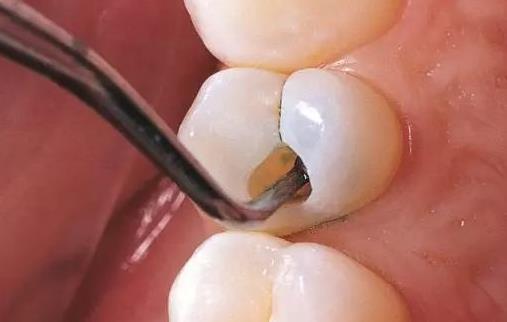

兒童補牙分為三個步驟:窩洞制備、充填補牙材料和清除殘渣。

1、窩洞制備:在補牙前需要對齲壞牙體進行窩洞的制作,建立良好的固位形和抗力形,以免充填體折斷、脫落和不密合而造成繼發齲。如果需要看孩子的牙根發育情況就要拍X線。

2、充填補牙材料:隔離唾液,消毒窩洞,調配充填材料填入窩洞中,雕刻外形。

3、清除殘渣:進行補牙材料填充后,牙科醫師會對牙面進行拋光及對附著在牙體周圍的殘渣進行清理。